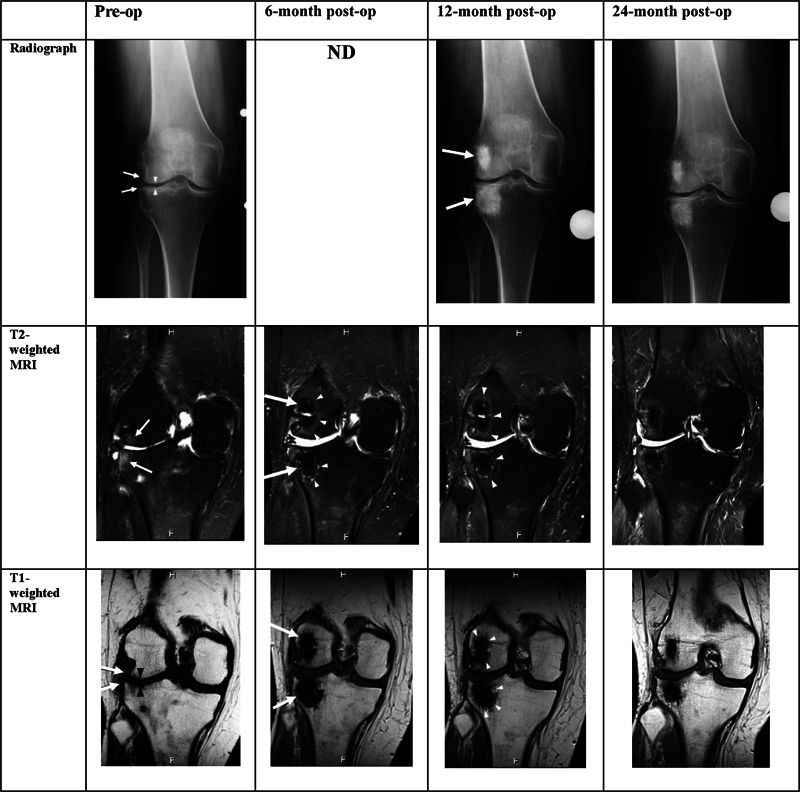

Bone marrow lesions (BMLs) have a strong correlation to patient-reported pain, functional limitations, joint deterioration, and rapid progression to total knee arthroplasty. The Subchondroplasty (SCP) procedure uses AccuFill, a calcium phosphate bone substitute material (BSM), to treat bone defects such as microtrabecular fractures and BML. This observational, prospective, multicenter, cohort study evaluated the effect of the SCP procedure at the 2-year follow-up for 70 patients with knee BML. Under arthroscopic and fluoroscopic guidance, the BML was injected with AccuFill. Patient-reported outcomes, including Visual Analog Scale (VAS) pain, Knee Injury and Osteoarthritis Outcome Score (KOOS), International Knee Documentation Committee (IKDC), and modified Knee Society Score (mKSS) were collected through 24 months postoperatively. Radiographs and magnetic resonance imaging (MRI) were performed at baseline and up to 24 months postoperatively. Patient selection was not limited based on the degree of osteoarthritis (OA) as determined radiologically by the Kellgren-Lawrence (K-L) grade. For a subset of patients, patient-reported outcomes were collected up to 5 years including pain evaluation, patient knee global assessment, and satisfaction with the procedure. Preoperative radiographs indicated moderate to severe OA (K-L grades 2-4) in 65 patients (92.8%). Significant improvements (p < 0.0001) in mean VAS pain, IKDC, mKSS, and KOOS scores were observed compared with baseline. Kaplan-Meier survivorship free from conversion to knee arthroplasty was 76.2% at 2 years. The subset of patients followed for 5 years demonstrated low pain scores and high procedure satisfaction. This study presents statistically significant and clinically meaningful evidence of improvement in clinical outcomes following SCP for BMLs of the knee after 2 years. The survivorship rate from arthroplasty at 2 years was 76.2%. SCP for BMLs can relieve pain with a minimally invasive procedure and may delay the need for knee arthroplasty. REGISTRATION:  NCT01621893 (ClinicalTrials.gov). LEVEL OF EVIDENCE:  Level II, Prospective Cohort Therapeutic Study.